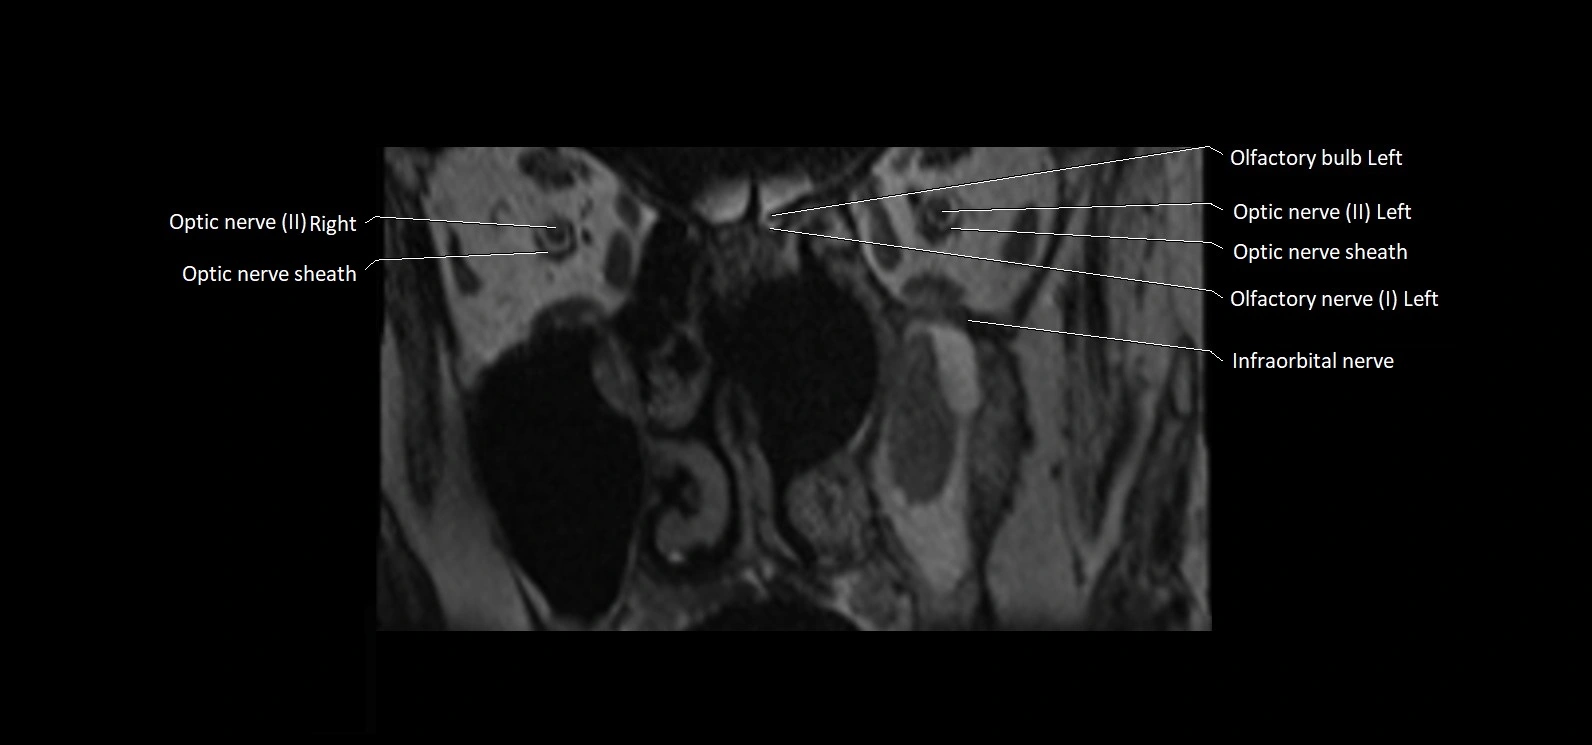

MRI Appearance

• The abducens nerve is a small, thin, linear structure

• Best visualized on high-resolution T2-weighted 3D MRI sequences (e.g., FIESTA or CISS)

• Seen as a hypointense (dark) line running from the brainstem at the pontomedullary junction, traversing the prepontine cistern, and entering Dorello’s canal under the petrosphenoidal ligament, then into the cavernous sinus, and finally the orbit

• May be challenging to visualize in standard MRI due to its small size

• Pathology may be inferred by absence, displacement, or enhancement of the nerve

MRI images

image